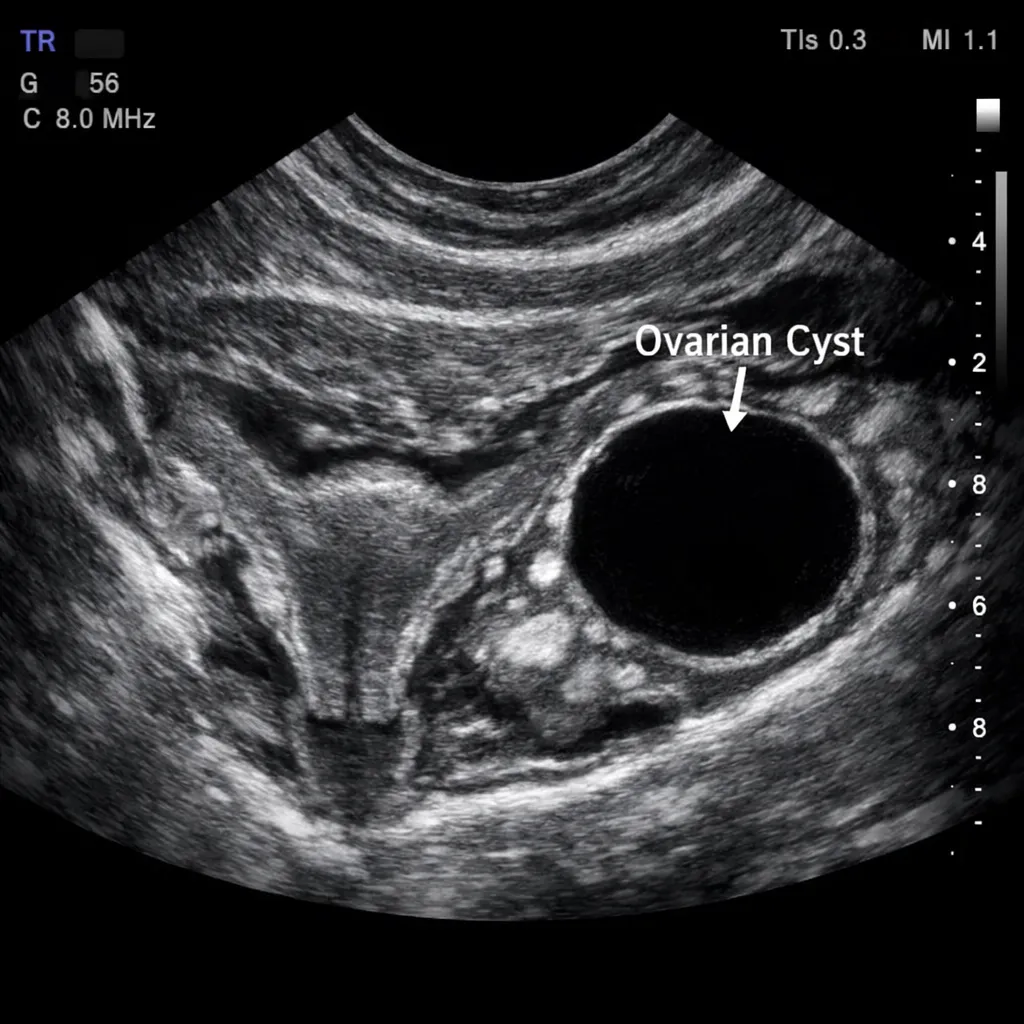

- Quistes ováricos y miomas (fibromas) uterinos

- Ultrasonido transvaginal: Evalúa ovarios (reserva folicular), útero y descarta quistes o miomas

Quistes Ováricos: Síntomas, Tipos y Cuándo Requieren Tratamiento

Los quistes ováricos son muy comunes en mujeres. Conoce los diferentes tipos, sus síntomas y cuándo es necesario buscar tratamiento médico.